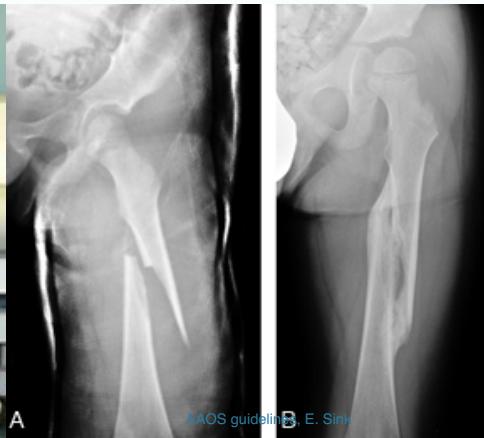

A 65 year old: slipped in the toilet

A 55 year old, tripped at edge of carpet

Radiological Evaluation

- Radiological evaluation

- AP and ?Lateral (cross-table)